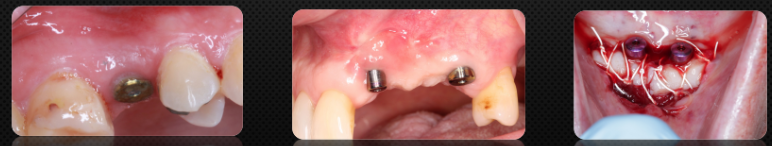

Soft tissue around implant

Peri-implant mucosal thickness and marginal bone loss

>2mm of thick tissue at the time of implant placement results in less marginal bone loss